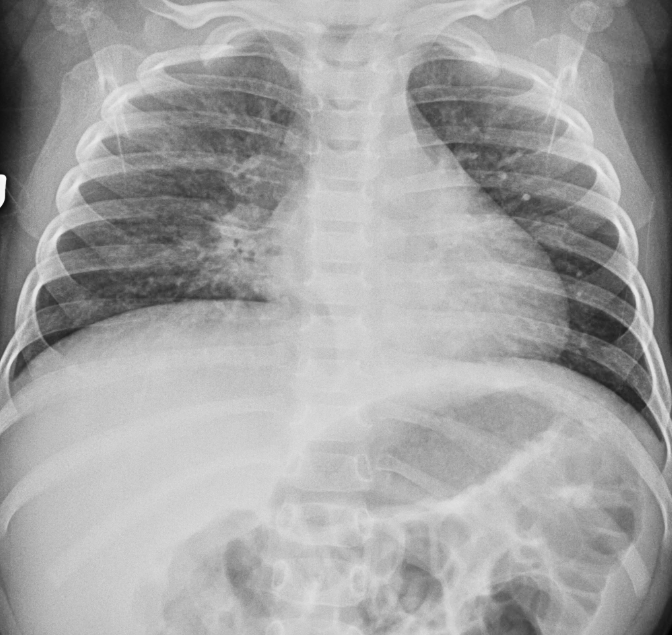

Peds Chest

Practice

Simulates call by including subtle or difficult cases and some normals.

50 cases